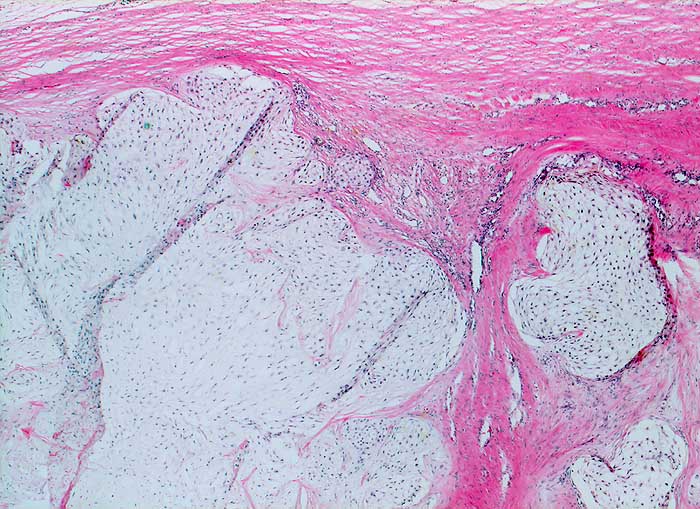

Die Zytologie des Chondrosarkoms ist charakterisiert durch neoplastische Chondrozyten auf einem Hintergrund von chondroider Matrix. Maligne Chondrozyten sind oval oder polygonal. Die Zellen sind locker kohäsiv oder liegen einzeln. Die Tumorzellen sind gelegentlich in Lakunen der hyalinen Matrix eingeschlossen. Vakuolisiertes oder granuläres Zytoplasma ist reichlich vorhanden. Die Kerne sind uniform, rund bis oval und können prominente Nukleolen enthalten. Zellreichtum, Kernatypien, Mehrkernigkeit und Mitosefiguren nehmen zu mit zunehmendem Tumorgrad. Bei den hochmalignen Chondrosarkomen enthalten die zellreichen Ausstriche fast ausschliesslich myxoide Matrix, die sich in der PAP Färbung schwach, in der MGG Färbung deutlich anfärbt.

Die verschiedenen Subtypten des Chondrosarkoms sind zytologisch wegen fliessender Übergänge nicht sicher zu unterscheiden. Die Kombination hohes Patientenalter, radiologische Zeichen eines destruktiven Wachstums, hohe Zellularität und Kernpolymorphie lassen bei knorpelbildenden Tumoren auf Malignität schliessen.